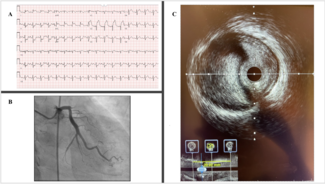

A 54-year-old man presented following a motor vehicle crash that resulted in a subarachnoid hemorrhage. Electrocardiogram showed anterolateral ST-segment elevations.